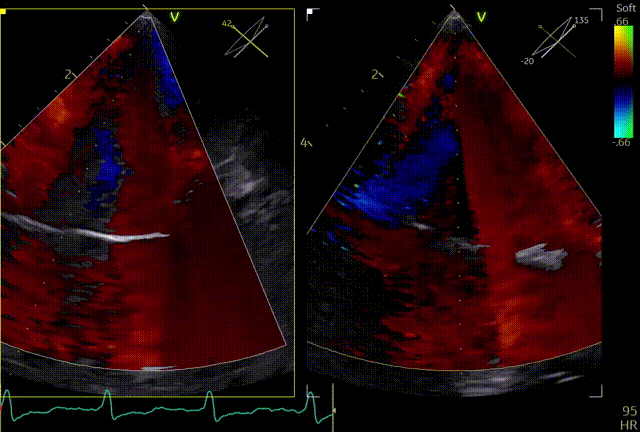

术前TTE

两腔心

短轴

四腔心zoom模式

反流情况